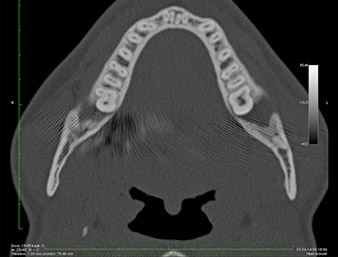

Der Wurzelrest regio 38 zeigte bereits in der Panoramaschichtaufnahme eine enge Lagebeziehung zum Nervus alveolaris inferior. (Abb. 1)

In der 3D-Aufnahme (digitales Volumentomogramm) war ersichtlich, dass sich der Wurzelrest weit disto-kaudal im Übergang vom horizontalen zum aufsteigenden Anteil des Unterkiefers befand (Abb. 2).

Unser Patient besaß anamnestisch gute Voraussetzungen (Nichtraucher, 26 Jahre) für einen erfolgreichen Eingriff. Wegen des Hinweises auf enge Lagebeziehung des Wurzelrestes zum N. alveolaris inferior in der Panoramaschicht-Aufnahme wurde zusätzlich eine digitale Volumentomografie erstellt (6).